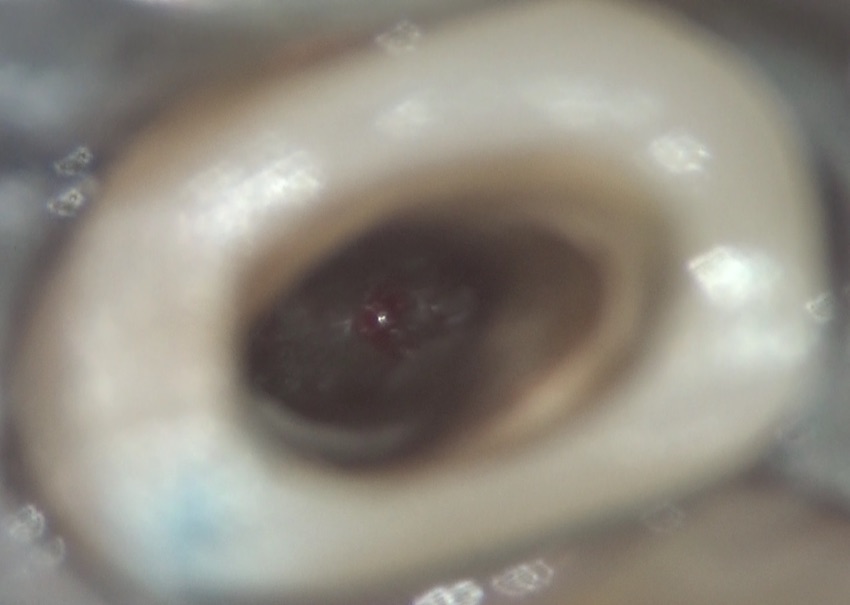

これが、キレイにし終わった際の、歯の内部の写真です。

この後、水酸化カルシウムを入れ、キャビトンで仮封をしました。